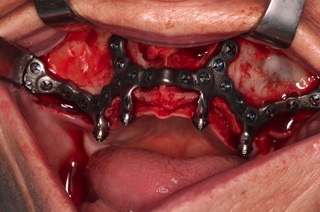

Estructura Subperióstica con carga inmediata maxilar

Paciente con atrofia total del hueso del maxilar que precisa rehabilitación. Se le realizó tratamiento con estructura subperióstica y el mismo día se le colocaron unos dientes fijos provisionales sobre la estructura.